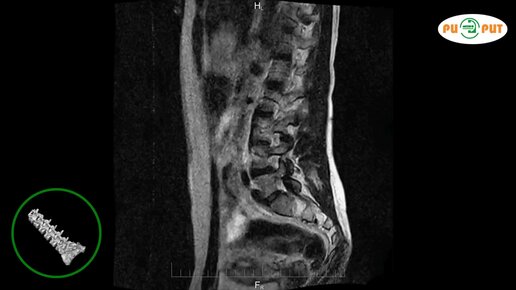

Как делают МРТ поясничного-крестцового отдела позвоночника